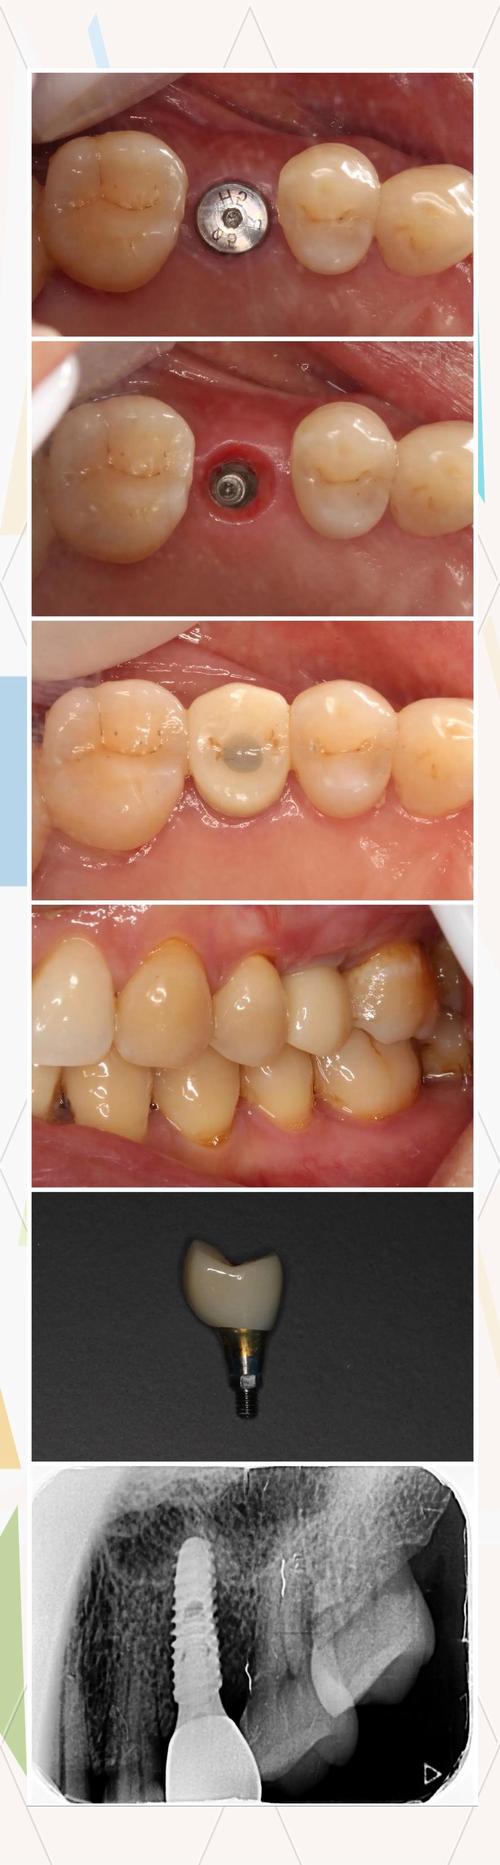

(图片来源网络,侵删)- 代表: 深圳有很多专注于种植牙的特色诊所,或由知名专家开设的个人诊所。

- 经验与案例: 了解医生从事种植牙的年限、完成种植案例的数量(尤其是类似你情况的案例),要求查看真实案例照片或视频。